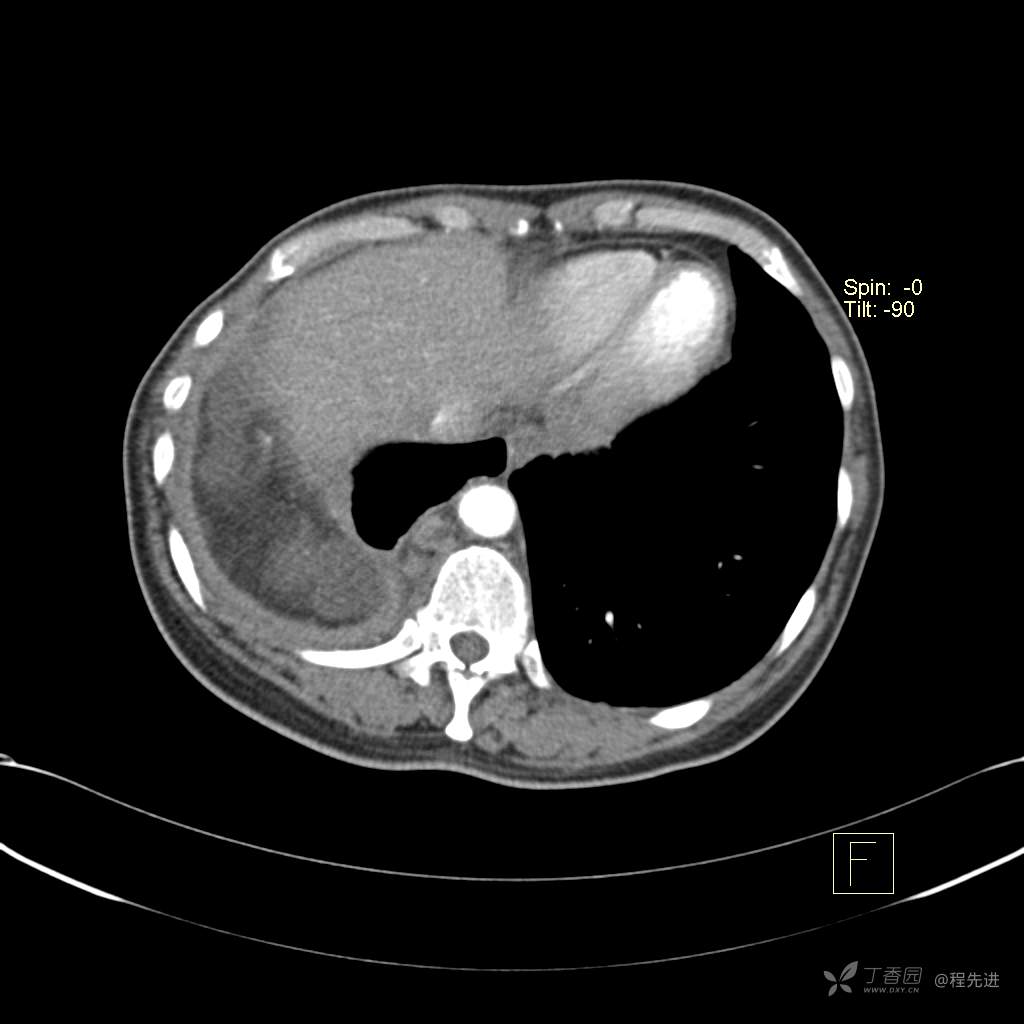

患者性别:女

患者年龄:51岁

简要病史:胸闷半年